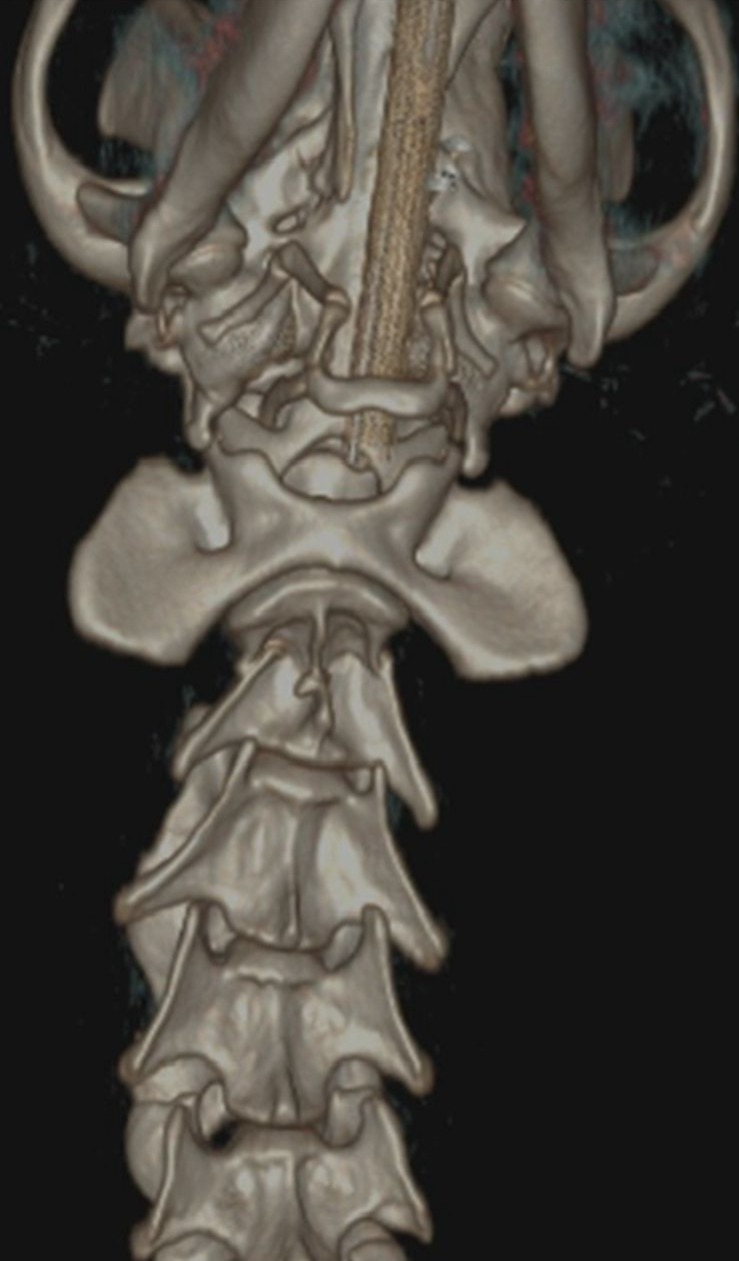

A thorough neurological examination followed by a CT scan revealed a C2 vertebral fracture with severe spinal cord compression along with a scapular fracture. Woody also experienced intense pain when flexing his neck. Given the risk of permanent damage, the surgical team decided to proceed with an advanced spinal fixation procedure using screws and PMMA.